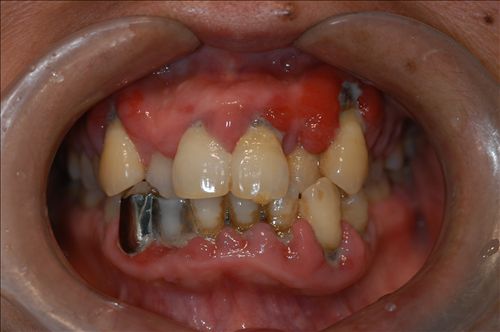

什么是牙周病

牙周病是指发生在牙齿周围支持组织(包括牙龈、牙周膜、牙槽骨、牙骨质)的感染性、炎症性、破坏性疾病。主要包括两大类,牙龈炎和牙周炎(牙龈炎可以发展为牙周炎)。牙周病的发病率很高,特别是在我国口腔卫生保健相对滞后的情况下,牙周炎是成人丧失牙齿的首要原因。